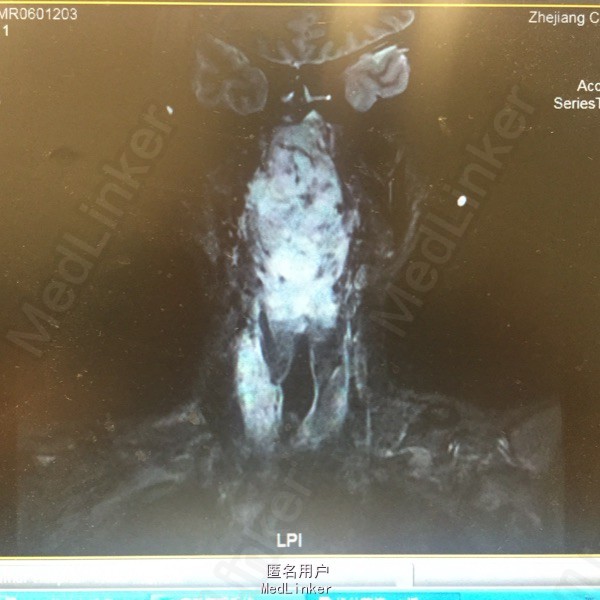

患者男性30岁。因进食困难伴吐血20天入院。患者8年前曾因鼻咽癌行放化疗,放疗资料遗失。近来出现进食困难,2度呼吸困难,近2周体重下降20公斤。

患者张口呼吸,口咽后壁可见巨大菜花样新生物。MRI提示:鼻咽、口咽巨大肿物向下累及右侧犁状窝。活检提示:首先考虑放疗后继发肌源性或纤维源性软组织肉瘤。

诊断:鼻咽癌放疗后继发软组织肉瘤 入院后行急诊气管切开,留置鼻饲营养管给予肠内营养改善全身情况。肿瘤生长迅速,目前给予表阿霉素及异环磷酰胺化疗,拟化疗后行手术切除。